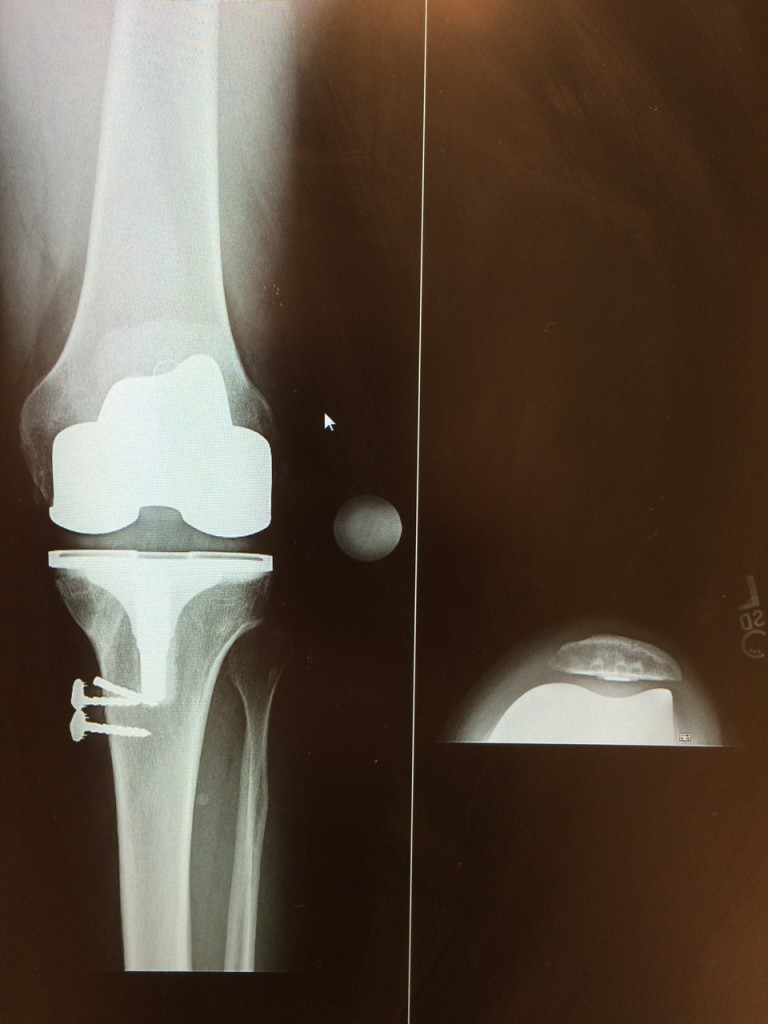

Being very young for a total Knee Replacement (TKR) I new that I would have to ride out the discomfort as long as I could. Knees today have new technology but average there life at 20 - 25 years. After that you receive a Revision Knee that will last 5-10. After this technology is used they have to fuse your leg straight. I was now facing one of the most important decisions of my life. With this I had researched 3 different products (Zimmer, Stryker, Smith and Nephew) 3 hospitals, and 3 different surgeons one of which has been my surgeon for over 12 years. At each surgeon visit I had 15 questions about the product and the hospital they worked at as far as product success and Hospital procedures. After gathering all of this information 3 keys of information is why I made my decision. Smith and Nephew's current knee technology, Dr. Steven Haas's technique's (which I watched on line from an operation he did with explanations of techniques he uses and why) and the Hospital that represents him. After researching the hospitals success in a nearly NO RATE of infections was enough for me to decide. As you can imagine growing up in such a meticulous industry I am extremely tough on protocols and procedures which equals successful results. This hospital is the best I have seen on so many levels. The surgeons, anesthesiologists, nursing staff put me at so much ease I was actually glad I was there that day and had no worries for putting my Life in their hands. Living in NJ in no way makes it convenient to choose HSS as my hospital, but their is no way I or YOU should ever make such a decision out of convenience.

My operation was one year ago and so far so good. Compared to some other people I know with the same operation my recovery time was cut in half compared to others. I went back to work 2 weeks after my operation although only for 4-5 hours. Although poorly I started golfing at month 3 again after departing the sport for 5 years due to pain. You can't imagine the feeling not being able to play soccer with your 8 yr old son. Now we play hockey etc. without a problem. 90% of the time I do not even realize "Simpson" is even in my body. I race quads with my sons and most importantly am back at work continuing to make our business a success for my children some day.